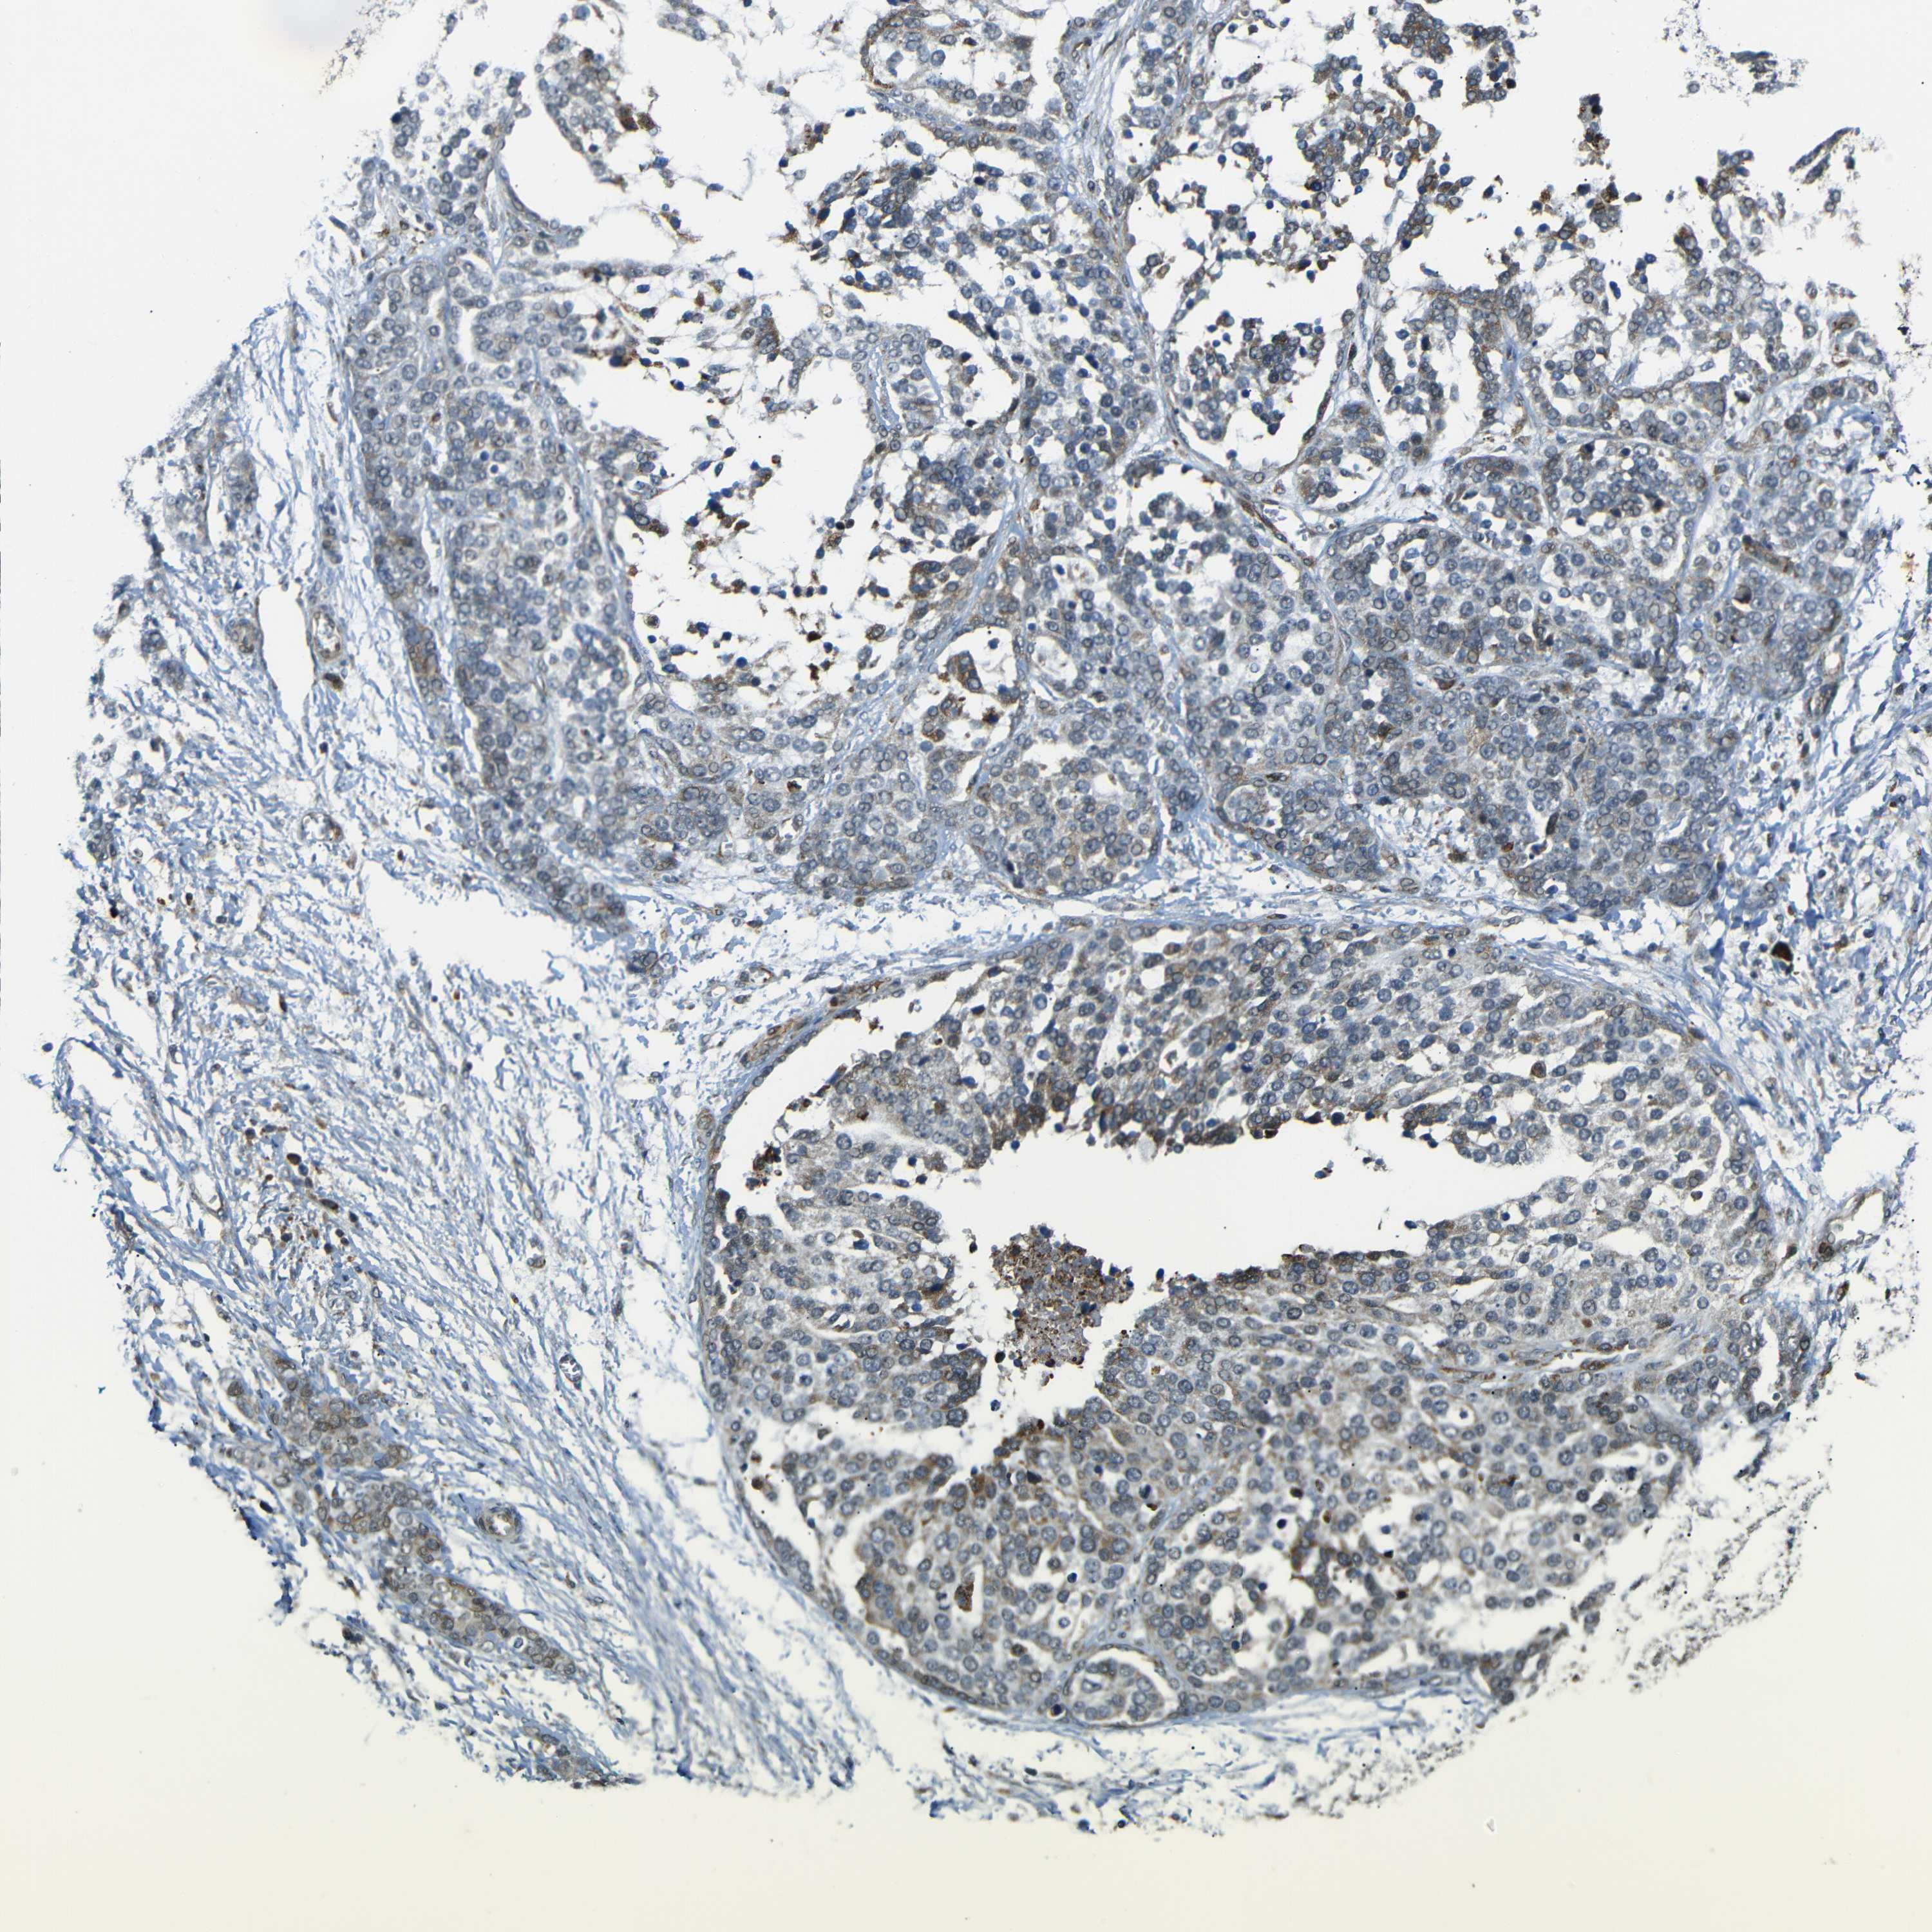

OVARIAN CANCER - Protein expressioni

A mouse-over function shows sample information and annotation data. Click on an image to view it in a full screen mode. Samples can be filtered based on level of antibody staining by selecting one or several of the following categories: high, medium, low and not detected. The assay and annotation is described here.

Note that samples used for immunohistochemistry by the Human Protein Atlas do not correspond to samples in the TCGA dataset.

Antibody stainingi

Antibody staining in the annotated cell types in the current human tissue is reported as not detected, low, medium, or high, based on conventional immunohistochemistry profiling in selected tissues. This score is based on the combination of the staining intensity and fraction of stained cells.

Each image is clickable and will lead to virtual microscopy that enables deeper exploration of all samples and also displays staining intensity scores, fraction scores and subcellular localization as well as patient and tissue information for each sample.

Antibody HPA013328

Staining

High

Medium

Low

Not detected

Intensity

Strong

Moderate

Weak

Negative

Quantity

>75%

75%-25%

<25%

None

Location

Nuclear

Cytoplasmic/membranous

Cytoplasmic/membranous,nuclear

Cystadenocarcinoma, serous, NOS

Carcinoma, endometroid

Cystadenocarcinoma, mucinous, NOS

Carcinoma, NOS